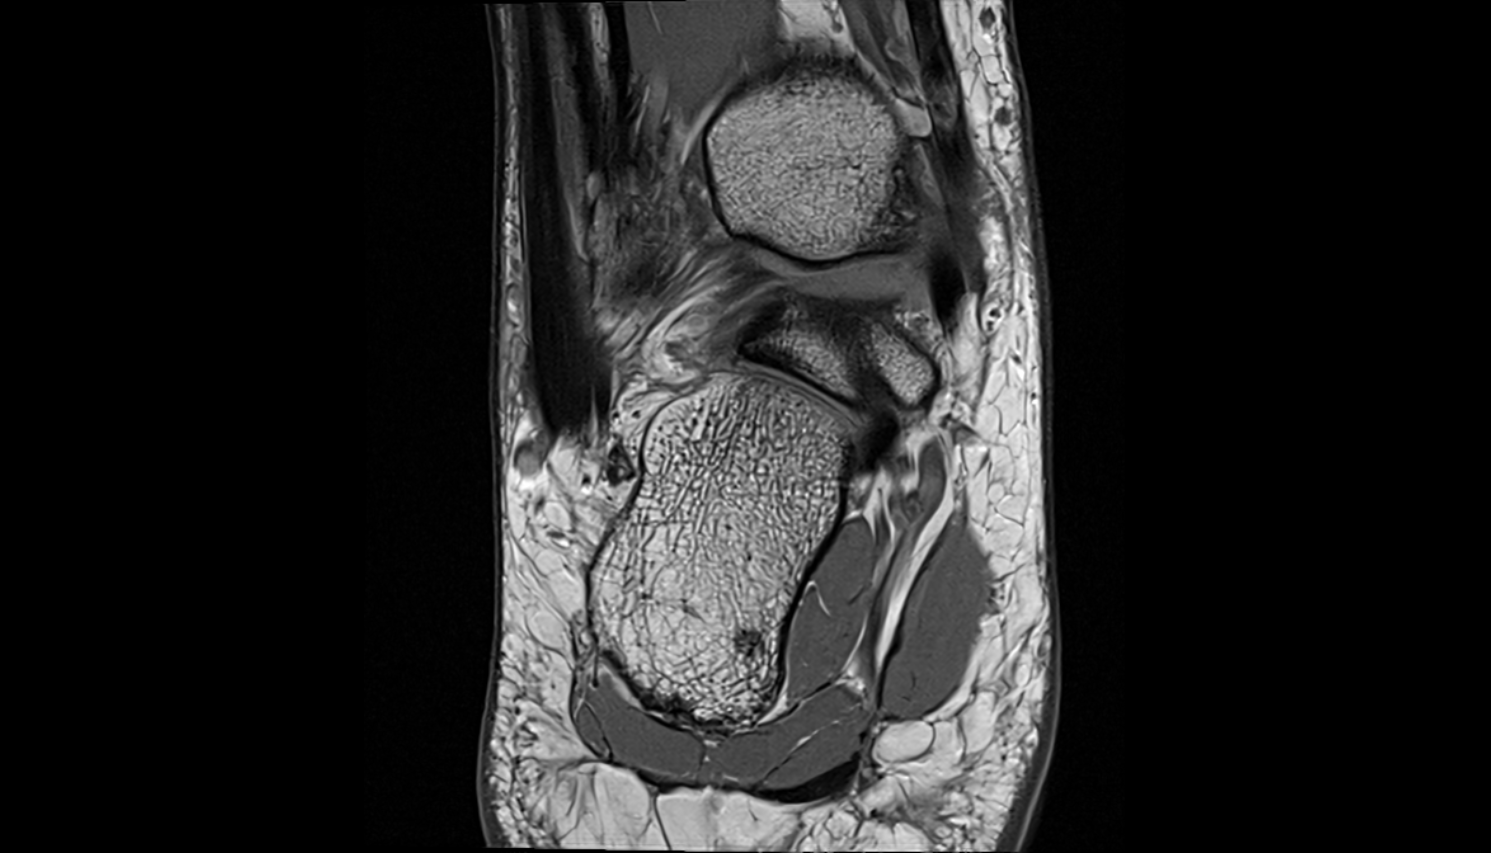

- Talus

- Head of talus

- Body of talus

- Neck of talus

- Calcaneus

- Ankle joint

- Talocalcaneal joint